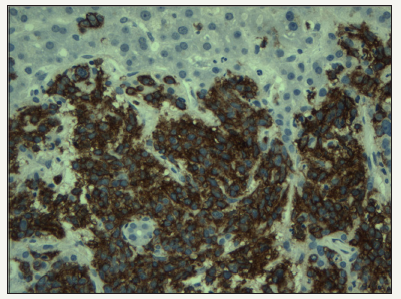

Most published series found that the most common type of hepatic primary lymphoma is diffuse large B-cell lymphoma, comprising 45% of the cases, followed by Burkitt lymphoma, lymphoblastic lymphoma, follicular lymphoma MALT lymphoma mantle cell lymphoma and T-cell lymphoma [1]. The cells are large with vesicular nuclei and prominent nucleoli. (Figure 1) from a hepatic mass biopsy is showing poorly differentiate malignant cells. This is required the application of proper immunohistochemical markers including CD45, CD20, CD5, CD10, CD79a, CD30, cyclin D, bcl2 and bcl6. The panel reveals lymphoma cells as the tumor cells were positive for CD45 lymphocyte marker. The cells were predominantly expressing CD20 (Figure 2), which is B-cell marker and support a diagnosis of large B cell lymphoma. Some subtypes of lymphoma like T-cell rich-B cell required molecular studies to establish the accurate diagnosis. Chronic lymphocytic leukemia/ small lymphocytic lymphoma tend to show portal infiltration. Other lymphoma type may show predominant diffuse infiltration [3-5].

Figure 1:High grade lymphoma mass lesion biopsy.